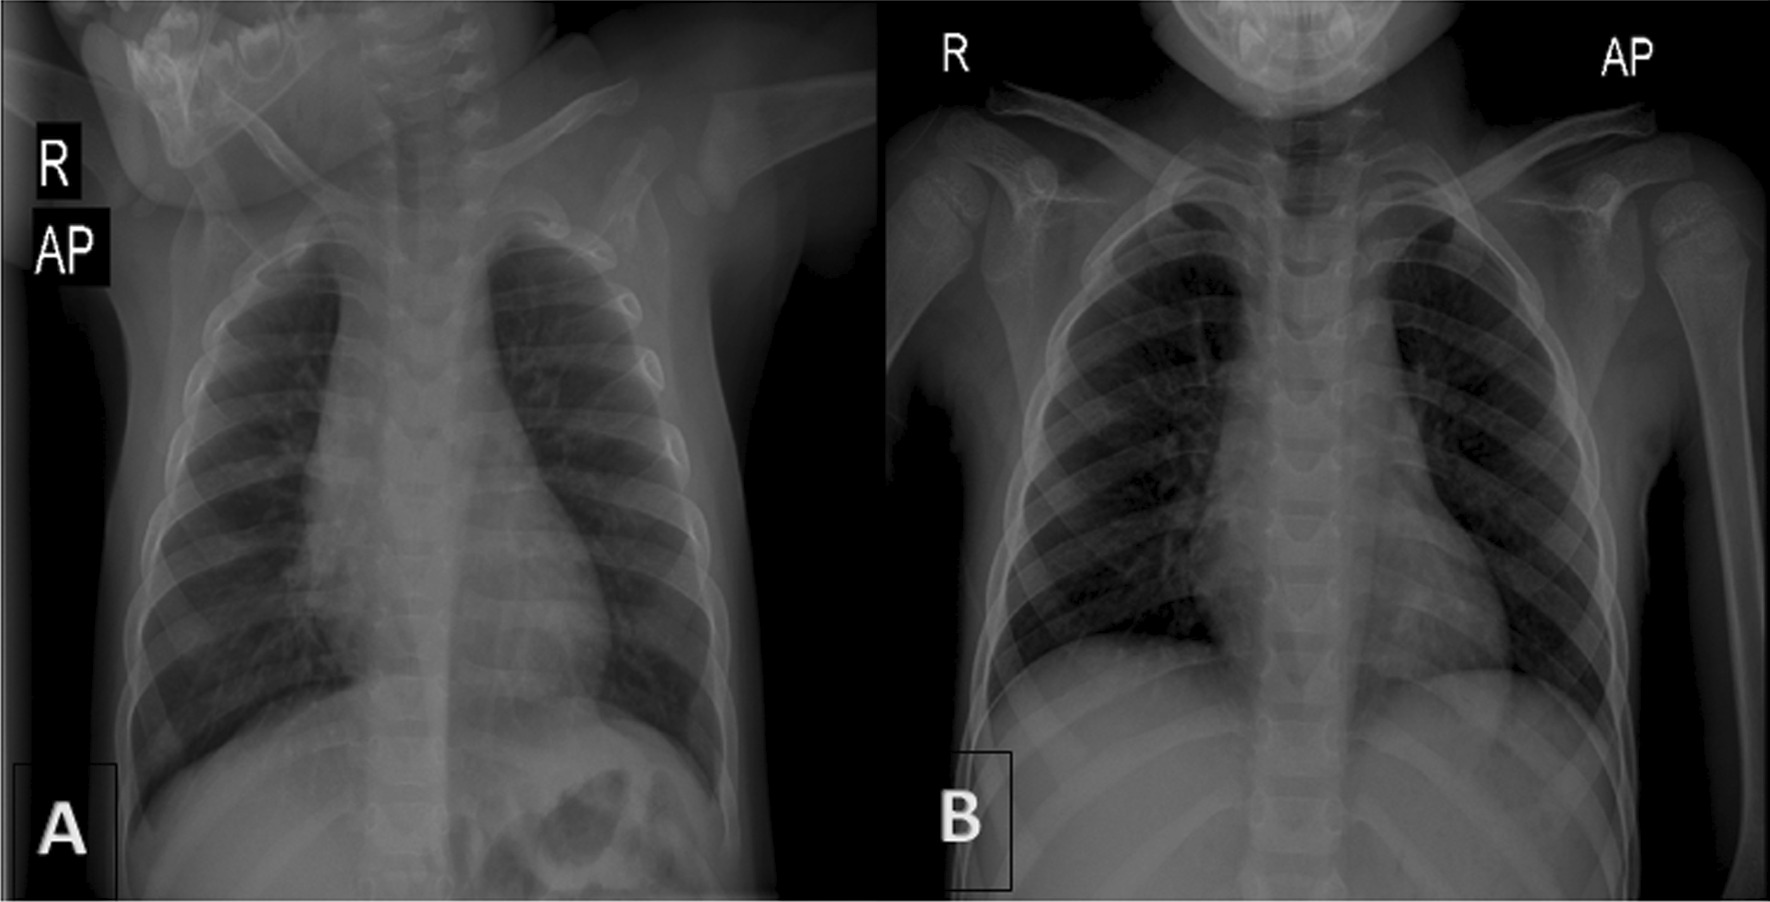

A 9-year-old persian boy was referred to the emergency department of the children’s hospital complaining of abdominal pain, inconstant in the left lower quadrant area, that started 3 days ago with an episode of nonbilious and nonbloody vomiting. The patient was born by cesarean section without any significant problems, and he had no history of underlying disease. He had been hospitalized twice, once at the age of 11 months because of pneumonia, and once when he was 5 years old owing to fever and cervical lymphadenopathy on the left side; after both admissions, he was discharged home in good general condition. In prior admissions, there was no sign of diaphragmatic herniation on chest x-ray (CXR) (Fig. 1A and B).

Fig. 1.

No sign of diaphragmatic herniation on previous CXRs (at age of 11 months, A) and (at age of 5 years, B)